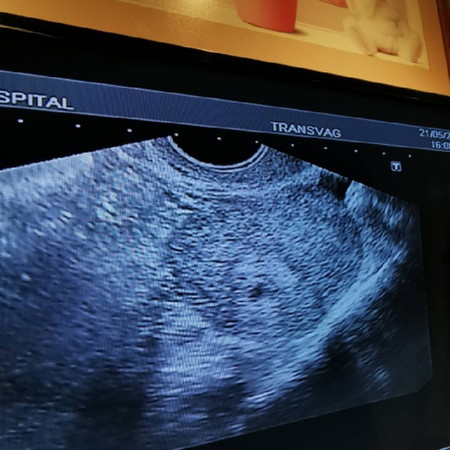

ขอบคุณแม่ๆทุกคนในห้องนี้มากนะคะ ? กระทู้เดิม 21/5/62 อายุครรภ์ประมาณ6วีค หมอ u/s ใช้เวลาประมาณ 1 นาทีไม่เกิน บอกว่าเจอแต่ถุงน้ำคร่ำ ไม่เจอตัวเด็ก ให้หยุดยาบำรุง แล้วทำใจ ? เราต่อลองบอกขออีก2วีคได้ไหมค่ะ เผื่อเค้าจะโต แล้วจะขอเจาะเลือดดู HCG หมอบอกไม่จำเป็น ตอนนี้เครียดมากเลยค่ะ คงจะเปลี่ยนหมอแล้วอยาก ให้อีกที่วินิจฉัยก่อนที่จะตัดใจว่าท้องลม ตอนนี้พยายามลุ้นให้ไข่ตกช้า มีคำแนะนำไหมค่ะ เคยแท้ง2ครั้ง ใน2ปี น้องไม่โตกับภาวะแท้งคุกคาม ➖➖➖➖➖➖ Update 30/05/62 จากวันที่ขอคำแนะนำ +7วัน เราได้คิวหมอที่ รพ.2 แล้วนะคะ เล่าประวัติการรักษาให้ฟัง คุณหมอบอกเคสเราเป็นการท้องเพราะได้รับ ฮอร์โมนกระตุ้นไข่ตก จากตอนที่ทำ หลอดแก้วเมื่อเดือนกุมภาพันธ์ ทำให้ไข่ตกไม่ปกติ ทำการ U/S ใหม่ถุงตั้งครรภ์โตขึ้น 5mm ➡️13.5mm. คุณหมอบอกขอเวลาอีก 2 วีค ให้เวลาน้องได้โต แล้วเรามาดูกันว่าจะมีปาฎิหาริย์ไหม เพราะน้องยังเล็กมาก เพราะตอนนี้คือจากผลแค่ 5 วีค ไม่ใช่7 วีค ตามปจด. ให้บำรุงต่อไปค่ะ จะมาอัปเดตอีกทีนะคะ ขอบคุณแม่ๆมากค่ะ ?

วันที่7พ.คเราไปฝากครั้งแรกตอน5w+4d ซาวหน้าท้องไม่เจอหมอเลยทำแบบ u/sค่ะ ก็เจอแต่ถุงตั้งครรภ์หมอบอกตัวเล็กมากน้องจะโตช้าหรือเปล่าเลยยังไม่ได้เจาะเลือดในวันนั้นรอคอนเฟิมให้แน่แต่หมอก็ให้ยาโฟลิคมากินนะคะแล้วนัดอีกทีวันที่21พ.ค แต่เราก็เครียดอยู่ดีกลัวเป็นท้องลมบ้าง กลัวน้องหยุดการเจริญเติบโตบ้างคิดไปต่างๆนาๆ แต่กลับบ้านมาเราก็กินยาไม่เคยขาดดื่มนม น้ำเต้าหู้ น้ำมะพร้าว ผัก ปลา จัดเต็ม😂 พอถึงวันที่21พ.คไปหาหมอ ซาวแบบ u/sเหมือนเดิม ก็เจอน้องเเล้วค่ะ คำแรกที่หมอพูดหัวใจน้องเต้นแล้วนะคะ ตอนนี้น้อง7w+6d เราดีใจแบบพูดไม่ถูกเลยคะ คุณแม่รออีกนิดนะคะ❤

อย่าพึ่งคิดมากนะคะ ของเราก็เป็นเหมือนกัน 6w3d u/sทางช่องคลอด เจอแต่ถุงตั้งครรภ์ไม่เจอตัวเด็ก มีประวัติแท้งตอน 12w 1ครั้ง รอการตั้งครรภ์ครั้งนานเกือบ 10 ปี เจอแบบนี้พูดไม่ออก แต่หมอนัดตามผลอีก 2 อาทิตย์ คือ 8w3d และระหว่างนั้นก็ทานยาโฟลิค คราวนี้เจอทั้งตัวเด็กและหัวใจเต้นเลยคะ ตามมาด้วยอาการแพ้แบบหนักหน่วง บางทีไข่อาจตกช้าทำให้ก็ไม่เจอตัวเด็ก ตอนนี้ 16w แล้วคะ ก็ยังคงต้องระวังและดูแลสังเกตตัวเองตลอด เป็นกำลังใจให้นะค่ะ

6 วีคเราไม่เจออะไรเลย ตรวจเลือด ค่าเลือดขึ้นแค่ 685 หมอนักอีก 1 วีค ตรวจเลือดอีกรอบ ซาวด์อีกรอบ ปรากฎว่าผลเลือดขึ้นเป็น 8 พันกว่าๆ ซาวด์แล้วเจอแต่ถุงตั้งครรภ์ ยังไม่เจอตัวเด็ก หมอเลยนัดอีก 2 อาทิตย์ คราวนี้นัดซาวด์อย่างเดียว เจอตัวอ่อนแล้ว หัวใจเต้นด้วย ไข่ตกช้าอ่ะของเรา ถ้านับจากประจำเดือนแล้วคือ 8 วีค แต่จริงๆแค่ 6 วีค กินยาต่อไปค่ะ อย่าหยุด น้องกำลังโต เปลี่ยนหมออื่นเลยค่ะ สู้ๆจ้า